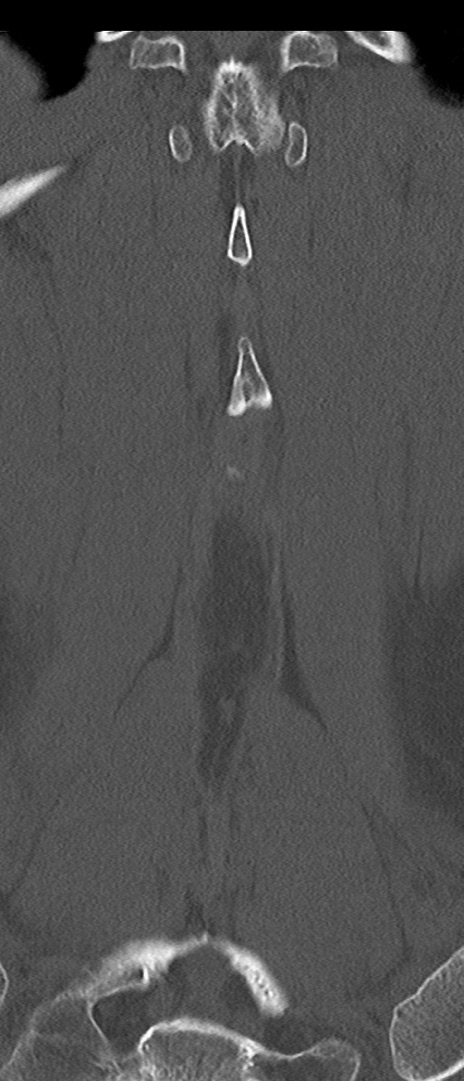

【整形】TIPS症例4 腰椎CT(冠状断像)

腰椎CT